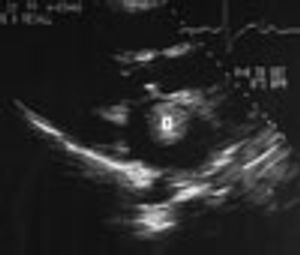

A 72-year-old man with a history of rheumatic heart disease presented with pulmonary congestion and syncope. Results of the cardiac examination suggested mitral stenosis and atrial fibrillation with a controlled ventricular response. Two-dimensional echocardi-ography revealed a large, free-floating ball thrombus (T) in the dilated left atrium and demonstrated rheumatic and severely stenotic mitral valve leaflets.